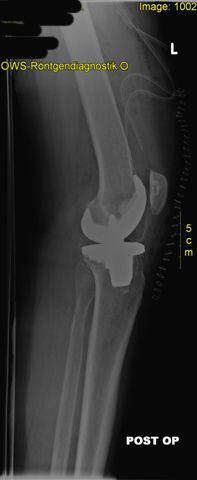

seitliche Ansicht einer Knievollprothese